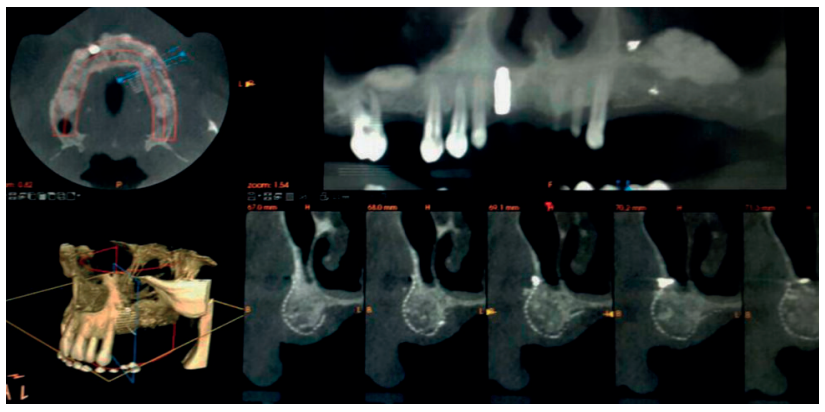

La regeneración localizada de grandes defectos horizontales en los procesos alveolares, previa a la inserción de implantes dentales, sigue siendo un procedimiento quirúrgico desafiante en cirugía bucal. Entre los procedimientos quirúrgicos más utilizados para tal propósito se encuentran la corticotomía con expansión, injerto en bloque “onlay” y la regeneración ósea guiada (ROG), todos ellos con sus diferentes grados de predictibilidad. El uso de micromalla de titanio en combinación con injertos y sustitutos óseos es un método eficiente para la contención, estabilización y protección de estos injertos, permitiendo así una mejor regeneración de los tejidos. Esta técnica no queda exenta de posibles complicaciones asociadas como pueden ser la infección, necrosis del injerto o exposición de la malla de titanio.

Localized regeneration of large horizontal defects in alveolar processes prior to the insertion of dental implants remains a challenging surgical procedure in oral surgery. Among the most widely used surgical procedures for this purpose are expansion corticotomy, onlay block graft and guided bone regeneration all of them with their different degrees of predictability. The use of titanium micromesh in combination with bone grafts and bone substitutes is an efficient method for the containtment, stabilization and protection of these grafts, thus allowing better tissue regeneration. This technique is not exempt from associated complications such as infection, graft necrosis or exposure of the titanium micromesh.

Se estima que la perdida ósea tras extracciones dentales es del 40-60% durante los tres primeros años, situación que crea modificaciones en el tejido duro en sentido vertical y horizontal5 . Este hecho, junto con la presencia de estructuras anatómicas nobles como el seno maxilar, cavidad nasal y nervio alveolar inferior con sus ramificaciones (nervio incisivo/mentoniano) son condicionantes que limitan el acceso al hueso disponible para la colocación de los implantes deseados para cada caso.

En los casos en los que se necesite un aumento óseo combinado en altura y anchura, las membranas no reabsorbibles fijadas con microtornillos serán el material más apropiado para una correcta fijación y estabilización del injerto. La complicación más común de las membranas no reabsorbibles es la exposición al medio bucal, que podrá generar infección y obligar la retirada prematura de la membrana provocando fracaso en el tratamiento3 .

Uehara S, Kurita H, Shimane T, Sakai H, Kamata T, Teramoto Y, Yamada S. Predictability of staged localized alveolar ridge augmentation using a micro titanium mesh. Oral Maxillofac Surg 2015; 19(4):411-6.